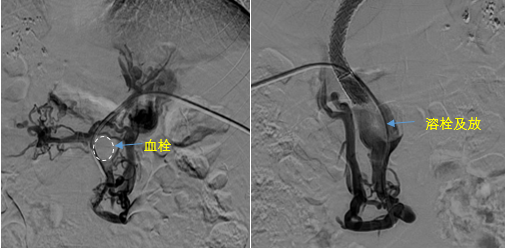

日前,西安國際醫學中心醫院消化病醫院為一位罕見巨大門靜脈血栓患者行TIPS手術。將患者體內的“定時炸彈”拆除。9月份的一天,李女士晚飯后發覺惡心,嘔吐出鮮紅色的血塊,隨即又出現了黑便。在醫院檢查發現是食管胃底靜脈曲張破裂出血。……